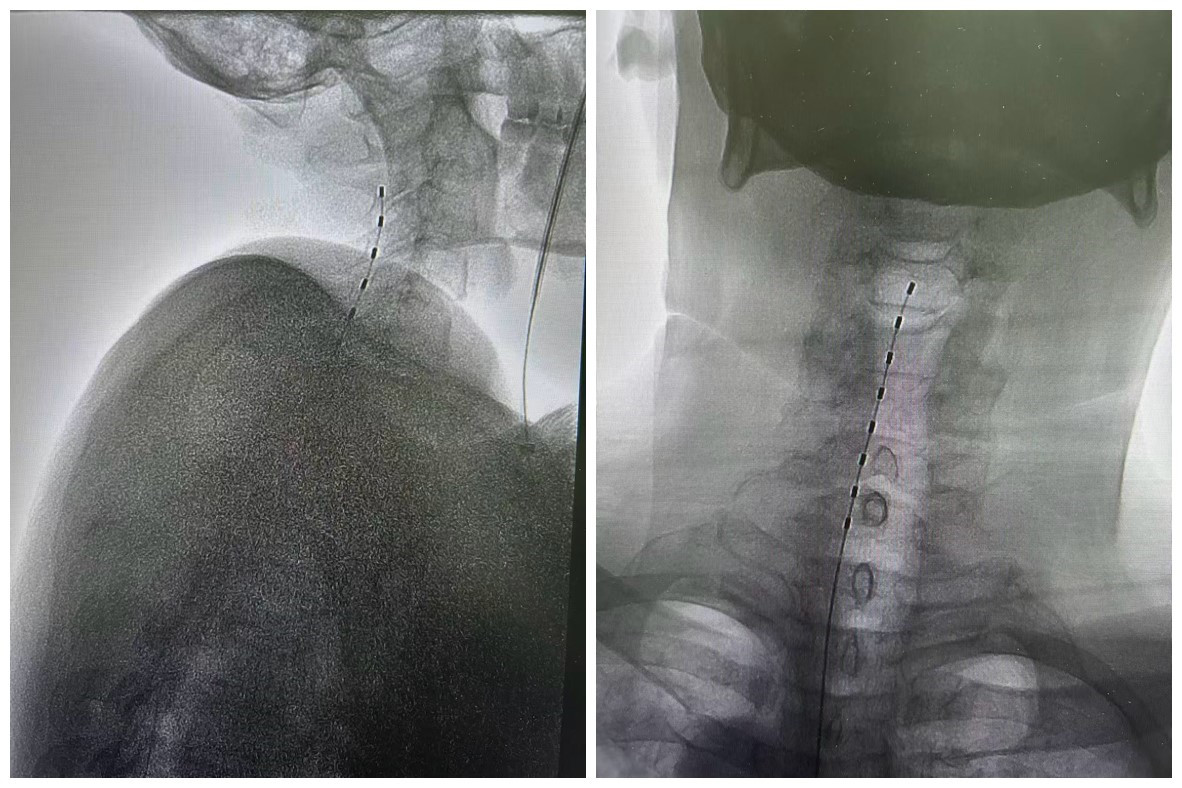

三个月前患者因脑出血遗留左侧肢体偏瘫,同时伴随左上肢肌张力增高及肢体疼痛,严重影响生活质量。神经外科团队经详细评估后,决定采用脊髓电刺激技术为其治疗。手术中,池超超副主任医师凭借精湛技术,通过穿刺方式精准植入电极,全程微创、创伤小。电极成功到位并开机后,患者当即反馈左上肢疼痛明显减轻,肌张力增高症状也同步缓解,治疗效果佳。

电极植入后影像

图片提供:神经外科 池超超